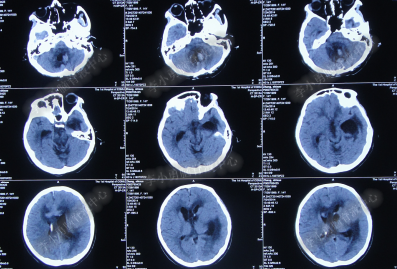

腰大池持续引流20天内,体温仍间断高热,曾3次脑脊液细菌培养均示鲍曼不动杆菌,先后使用利奈唑胺+克倍宁,利奈唑胺+克倍宁+奥硝唑,舒普深+米诺环素+来立信+氟康唑,舒普深+米诺环素+美罗培南+氟康唑,及日达仙、人免疫球蛋白提高免疫力,但颅内感染仍控制不住,期间多次头部CT检查均示脑室无明显扩张(图-7、图-8、图-9)。

图-7:2014年6月9日头部CT

图-8:2014年6月14日头部CT

图-9:2014年6月21日头部CT